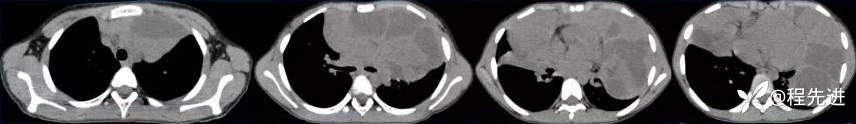

CT

平扫

纵隔窗